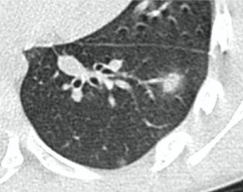

2. Наличие клинических проявлений, указанных в п. 1, в сочетании с характерными изменениями в легких по данным компьютерной томографии (КТ) (см. Приложение 1 настоящих рекомендаций) вне зависимости от результатов однократного лабораторного исследования на наличие РНК SARS-CoV-2 и эпидемиологического анамнеза.

- Изменения при КТ (рентгенографии), типичные для вирусного поражения (объем поражения минимальный или средний; КТ 1 - 2)

- Изменения в легких при КТ (рентгенографии), типичные для вирусного поражения (объем поражения значительный или субтотальный; КТ 3 - 4)

- Изменения в легких при КТ (рентгенографии), типичные для вирусного поражения критической степени (объем поражения значительный или субтотальный; КТ 4) или картина ОРДС.

КТ имеет высокую чувствительность в выявлении изменений в легких, характерных для COVID-19. Применение КТ целесообразно для первичной оценки состояния ОГК у пациентов с тяжелыми прогрессирующими формами заболевания, а также для дифференциальной диагностики выявленных изменений и оценки динамики процесса. КТ позволяет выявить характерные изменения в легких у пациентов с COVID-19 еще до появления положительных лабораторных тестов на инфекцию с помощью МАНК. В то же время, КТ выявляет изменения легких у значительного числа пациентов с бессимптомной и легкой формами заболевания, которым не требуется госпитализация. Результаты КТ в этих случаях не влияют на тактику лечения и прогноз заболевания при наличии лабораторного подтверждения COVID-19. Поэтому массовое применение КТ для скрининга асимптомных и легких форм болезни не рекомендуется.